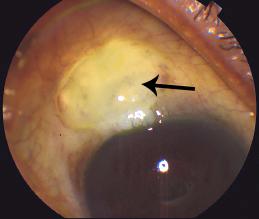

当青光眼的病人在进行手术的时候,眼科醫生使用病人自身的鞏膜組織來製造可調節房水流出的活瓣(Flap),活瓣上面會用結膜組織覆蓋,當房水從活瓣處流出時,就會積存在結膜下,外觀看起來像一個小水泡,這個小水泡即是濾過泡(Bleb)(圖1),其所在處便是手術新創造的過濾區(Filtration Site)。

3.使用細小的針進入發生疤痕組織阻塞的地方,將疤痕組織挑開、分離,直至恢復活瓣通道的通暢。若滿足以下指標,則可認為治療成功:1. 見到有房水流出積存在濾過泡處,濾過泡形成良好(圖2);2. 眼壓下降(最好是10-15mmHg);3. 前房深度合適。